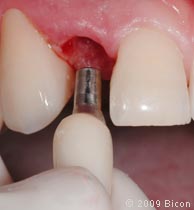

29. Удаление излишков мягких тканей, которые могут препятствовать правильной установке трансфера, производится посредством слепочного римера размером 3 мм, вращаемого вокруг направляющего штифта.

32. Установка пластикового слепочного трансфера в имплантат.